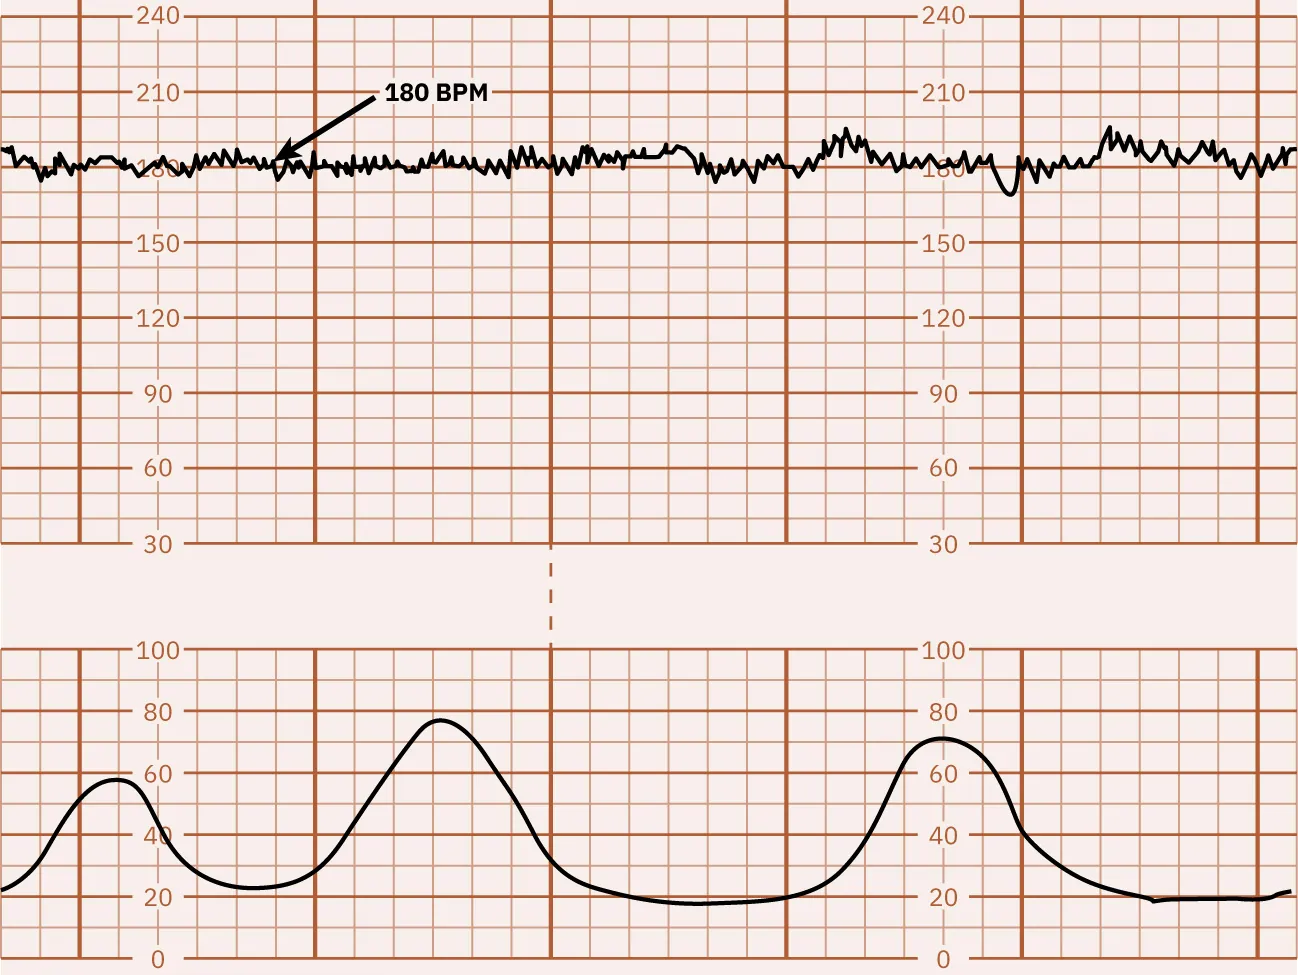

Tachycardia

An FHR baseline greater than 160 bpm for 10 minutes is called tachycardia. Figure 16.3 shows a monitor tracing that indicates FHR tachycardia. Tachycardia can be caused by multiple factors. A common cause of FHR tachycardia is the presence of fever in the pregnant person. Tachycardia should not be considered a sign of fetal distress in the absence of FHR decelerations. Other risk factors for tachycardia are listed in Table 16.1. Many of these can be addressed, and the FHR will return to normal.

Fetal heart rate reading indicating tachycardia.

Figure 16.3 Tachycardia This monitor tracing indicates tachycardia, which is defined as the sustained elevation of fetal heart rate baseline above 160 bpm for 10 minutes. (attribution: Copyright Rice University, OpenStax, under CC BY 4.0 license)